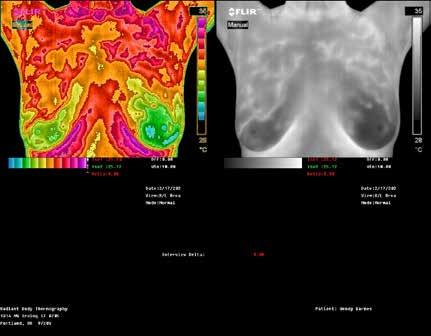

RADIANT BODY

THERMOGRAPHY

REDUCE YOUR RISK WITH NO RISK TO YOUR HEALTH!

TOP: Thermographic pattern of physician-confirmed estrogen dominance, which the client addresses. BOTTOM: Images show success in removing the estrogen dominance pattern & client also downgrades her abnormal right breast! Estrogen dominance has a heat signature visible with QUALITY Thermography.